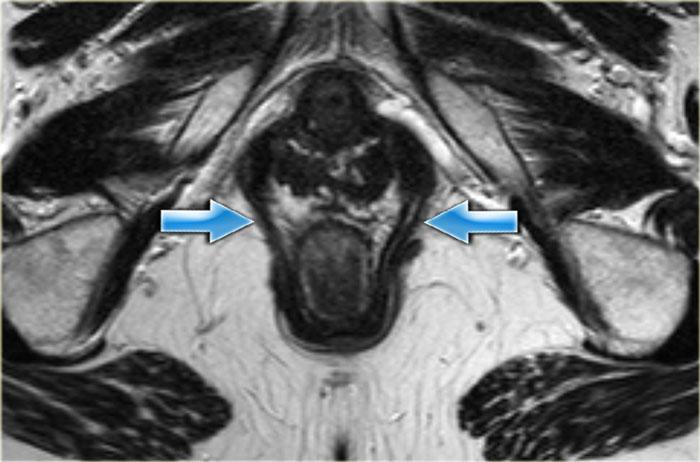

Trên các hình ảnh MRI mặt phẳng axial và coronal, các lớp khác nhau của cơ thắt hậu môn cùng các cấu trúc xung quanh có thể được hiển thị một cách rõ nét và chi tiết.

Cơ thắt hậu môn bao gồm ba lớp:

- Cơ thắt trong: là phần tiếp nối của lớp cơ trơn vòng của trực tràng, hoạt động không tự chủ, co lại khi nghỉ ngơi và giãn ra khi đại tiện.

- Khoang liên cơ thắt.

Cơ thắt ngoài: cơ vân hoạt động tự chủ, được chia thành ba lớp hoạt động như một đơn vị thống nhất.

Ba lớp này liên tục với cơ mu-trực tràng và cơ nâng hậu môn ở phía trên (hình minh họa).

Cơ mu-trực tràng có nguyên ủy từ hai bên khớp mu, tạo thành một ‘vòng đai’ bao quanh vùng trực tràng-hậu môn.

Cơ mu-trực tràng co lại khi nghỉ ngơi và tạo ra góc gập 80° tại vùng nối trực tràng-hậu môn.

Cơ này giãn ra trong quá trình đại tiện.